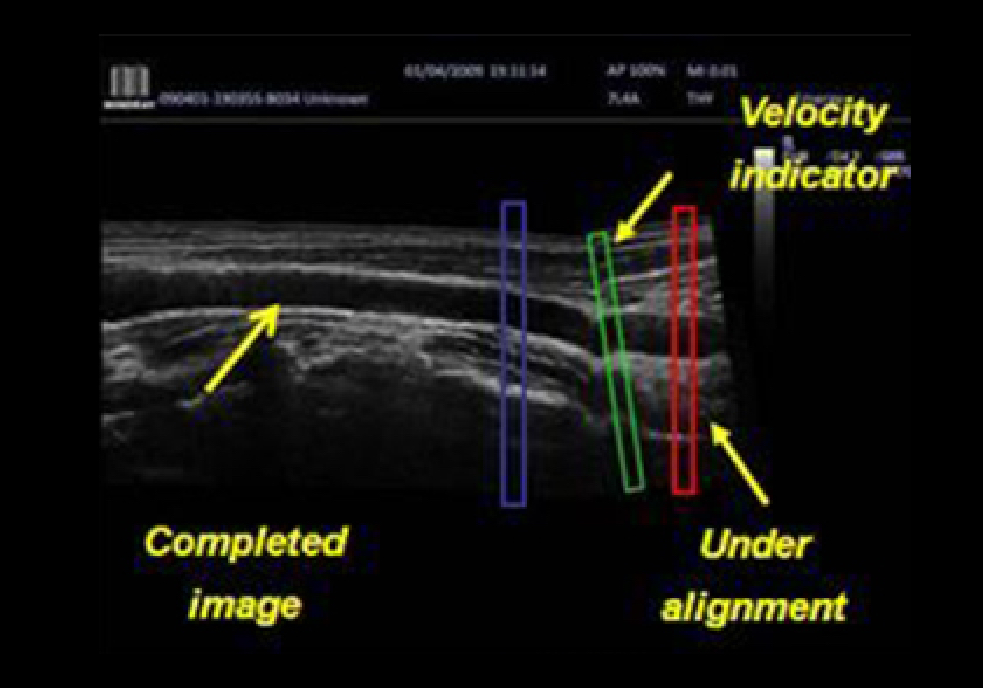

iScapeTM (Real-time Panoramic Imaging)

Get a complete and extended view of the anatomical structure through panoramic imaging, coupled with velocity indication and forward/backward scan ability making scanning much easier, smoother and more controllable.